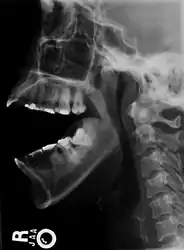

Sagittal section of the articulation of the mandible. | |

As with other joint dislocations, clinical history and examination are important for diagnosis. Commonly, plain and panoramic X-rays are used to determine the relative position of the mandibular condyle. If a complex or unusual injury is suspected, computed tomography is most reliable in diagnosing dislocation and possibly associated fractures or soft tissue injuries.

- Bilateral anterior dislocation of the jaw

- Jaw dislocation following relocation

- CT image demonstrating jaw dislocation